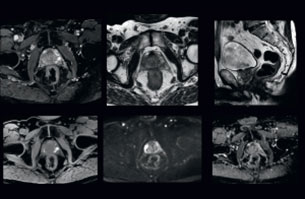

A 63-year-old patient with prostate cancer, cT3bNxM, Gleason 7, underwent MRI on Ingenia 3.0T MR-RT before radiation therapy.

Intraprostatic lesions are visible on the bTFE MR image, but not on the CT image. MRI shows excellent soft-tissue contrast for the visualization of critical structures like the rectum and penile bulb.

Fiducial markers (green arrows) are used in registration of MR images to CT, to transfer the MR-based delineations onto the CT image dataset.